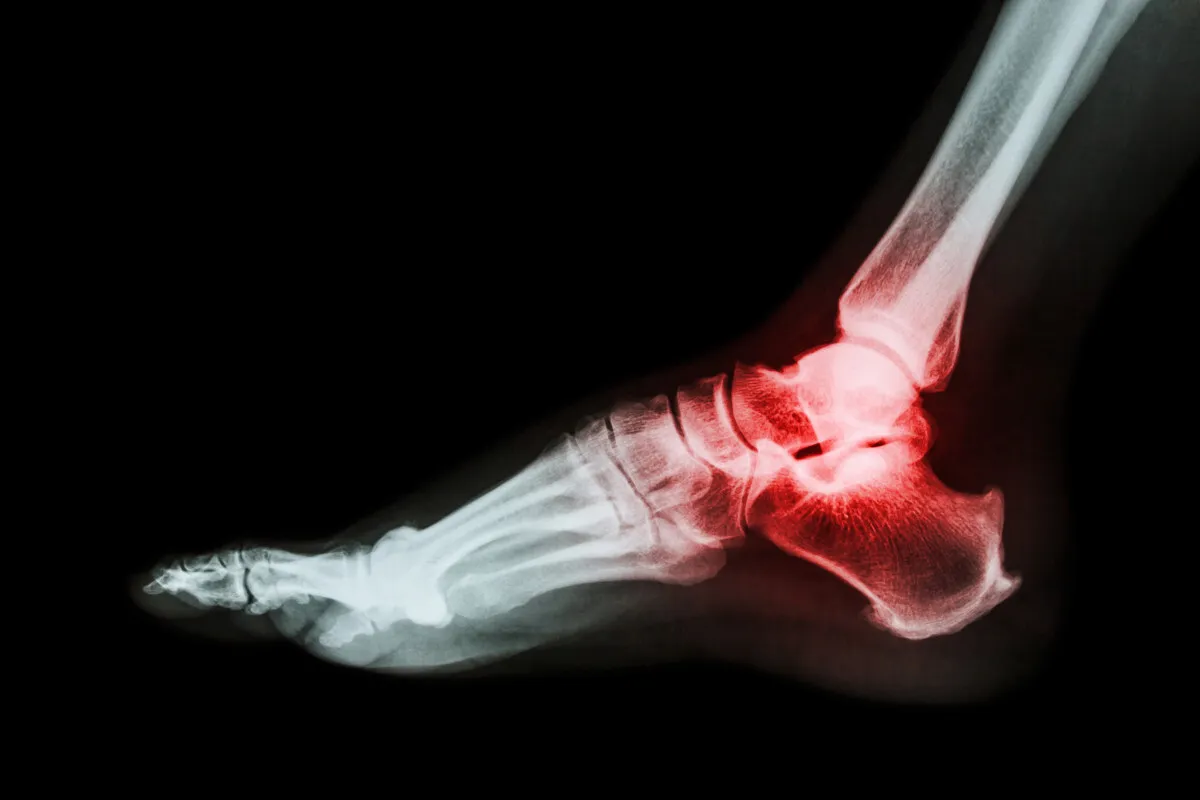

Jako fizjoterapeuta z doświadczeniem, mogę śmiało powiedzieć, że złamanie kości piętowej to jeden z najbardziej wymagających urazów pod kątem rekonwalescencji. Określenie precyzyjnego czasu rehabilitacji jest niezwykle trudne, ponieważ proces ten jest głęboko indywidualny. Kość piętowa, czyli calcaneus, jest fundamentem naszej stopy, kluczowym dla obciążania i amortyzacji. Jej uszkodzenie wpływa na całą biomechanikę chodu, a co za tym idzie, na każdy aspekt naszego życia. Nie ma jednej, prostej odpowiedzi na pytanie o długość powrotu do zdrowia, co często frustruje pacjentów, ale jest to niestety rzeczywistość. Musimy być przygotowani na to, że droga do pełnej sprawności może być długa i kręta.

Złamanie kości piętowej jest szczególnie problematyczne w porównaniu do innych złamań, na przykład kości przedramienia czy obojczyka. Wynika to z kilku kluczowych aspektów anatomicznych i funkcjonalnych. Po pierwsze, kość piętowa jest głównym punktem podparcia naszej stopy, przenoszącym większość ciężaru ciała podczas stania i chodzenia. Jest również kluczowa dla amortyzacji wstrząsów, chroniąc stawy wyżej położone, takie jak kolano czy biodro, a nawet kręgosłup.

Po drugie, kość piętowa tworzy skomplikowany staw podskokowy (skokowo-piętowy), który odpowiada za ruchy inwersji i ewersji stopy, niezbędne do adaptacji stopy do nierównego podłoża. Złamania śródstawowe, czyli te obejmujące powierzchnie stawowe, są szczególnie groźne, ponieważ mogą prowadzić do trwałego uszkodzenia chrząstki stawowej i wczesnego rozwoju zmian zwyrodnieniowych. Uszkodzenie kości piętowej wpływa więc na całą biomechanikę chodu, prowadząc do kompensacji w innych częściach ciała i potencjalnych problemów w przyszłości. Dlatego tak ważne jest, aby rehabilitacja była prowadzona z najwyższą starannością i precyzją.